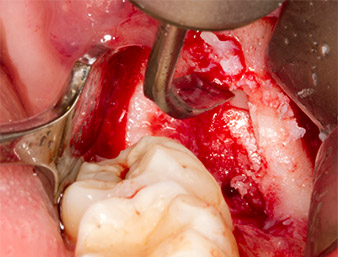

Dopo l'anestesia tronculare e l'anestesia locale, il sito operatorio è stato aperto e il tessuto molle esposto per l'accesso retromolare boccale (Fig. 3).

incisione sulculare

Fig. 3: L'incisione sulculare ha inizio a metà del dente 36 (LL6), con estensione distale sul ramo ascendente.

Il tessuto al di sopra del residuo di radice non era completamente ossificato ed era costituito per la maggior parte da tessuto di granulazione modificato dall'infiammazione (Fig. 4).

Tessuto di granulazione

Fig. 4: Due retrattori Langenbeck e una curette espongono l'area dell'intervento. È visibile il tessuto di granulazione della prima osteotomia non completamente cicatrizzata.